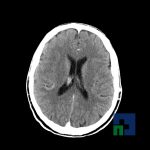

Examinare de rutină cerebrală, nativ și cu substanță de contrast (SDC) pentru diagnosticul:

- Accidentelor vasculare cerebrale ischemice sau hemoragice

- Evaluarea deplasării liniei mediane

- Evaluarea cisternelor perimezencefalice

- Diagnosticul edemului cerebral, a contuziei cerebrale, a leziunilor axonale difuze edematoase/hemoragice, a dilacerării cerebrale, a hematomului intraparenchimatos posttraumatic, a hematoamelor subdurale/extradurale (acute, subacute, cronice), a hemoragiei intraventriculare, a hemoragiei subarahnoidiene